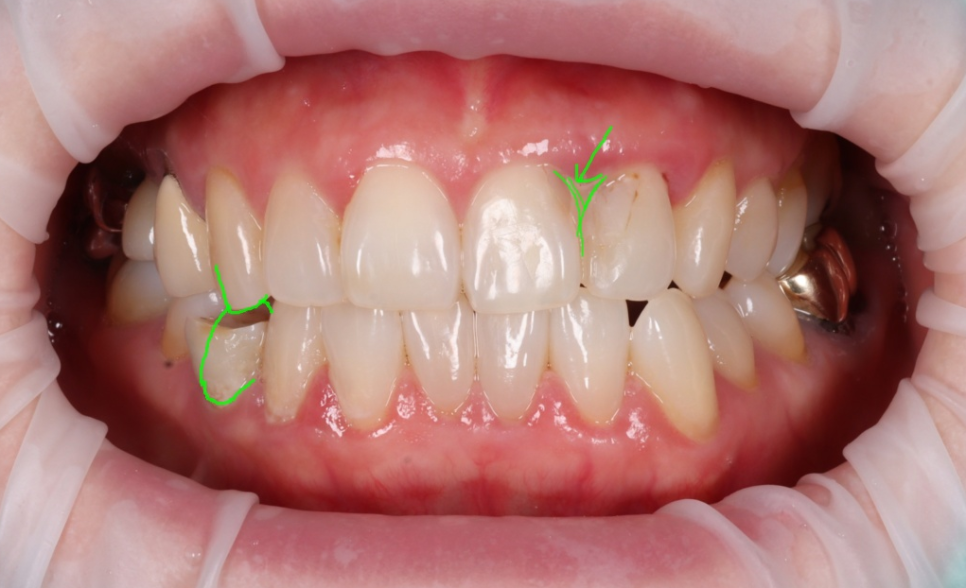

모든 과정을 마치고 환자분께서 "원장님, 이제야 정말 제 치아 같아요. 마음 놓고 크게 웃을 수 있겠어요!"라며 기뻐하시더라고요ㅎㅎ

촬영일 : 251230

저 또한 환자분이 겪으셨던 마음고생을 잘 알기에 큰 보람을 느꼈던 순간이었습니다.

주변 치아와 구분이 안 갈 정도로 자연스러운 투명감을 되찾았고 무엇보다 이제는 치실이 부드럽게 통과하며 잇몸을 깨끗하게 관리할 수 있게 되었죠^^

1주 뒤, 경과체크를 했습니다.

260107

잇몸이 아주 잘 아물었습니다.

잇몸 라인이 건강하게 정리되니 웃을 때 치아도 훨씬 황금비율에 가까워졌는데요.

또한 왼쪽 아래 어금니도 지르코니아로 씌워 심미와 기능 모두 회복하셨습니다.

251230/260107